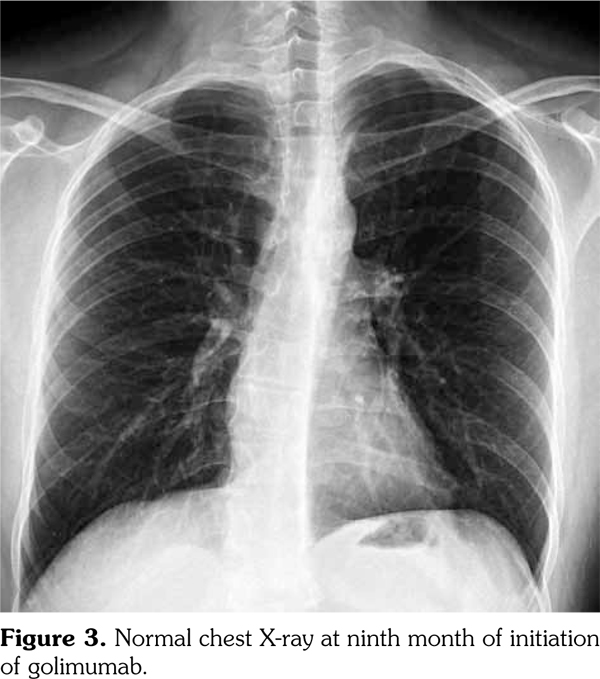

A 29-year-old male patient who had AS for 13 years applied to our rheumatology outpatient clinic for routine yearly control. His AS had been under control with etanercept for 43 months. After the routine follow-up evaluation, a thorax computed tomography scan was performed because of hilar enlargement in the chest X-ray. Multiple lymphadenopathies, the largest one with 2 cm in diameter, were detected in computed tomography scan (Figure 1).